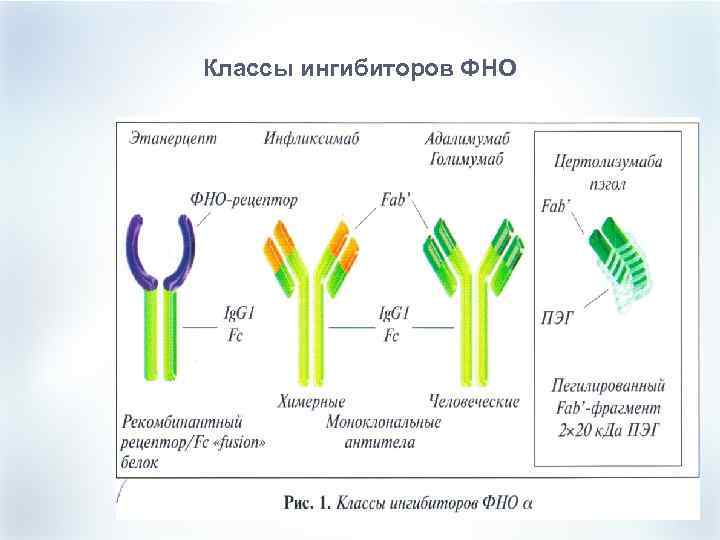

Эра биологической терапии (ГИБПгенно-инженерные базисные препараты). Цель терапии- достижение ремиссии, а не только симптоматическое улучшение и замедление прогрессирования деструкции процесса. ГИБП- Селективно блокируют важные звенья иммунопатогенеза РА. Ингибиторы ФНО-α: ФНО-рецептор : ЭТАНЭРЦЕПТ Химерные м. АТ к ФНО-α: ИНФЛИКСИМАБ Человеческие м. АТ к ФНО-α: АДАЛИМУМАБ

Эра биологической терапии (ГИБПгенно-инженерные базисные препараты). Цель терапии- достижение ремиссии, а не только симптоматическое улучшение и замедление прогрессирования деструкции процесса. ГИБП- Селективно блокируют важные звенья иммунопатогенеза РА. Ингибиторы ФНО-α: ФНО-рецептор : ЭТАНЭРЦЕПТ Химерные м. АТ к ФНО-α: ИНФЛИКСИМАБ Человеческие м. АТ к ФНО-α: АДАЛИМУМАБ

Классы ингибиторов ФНО

Классы ингибиторов ФНО